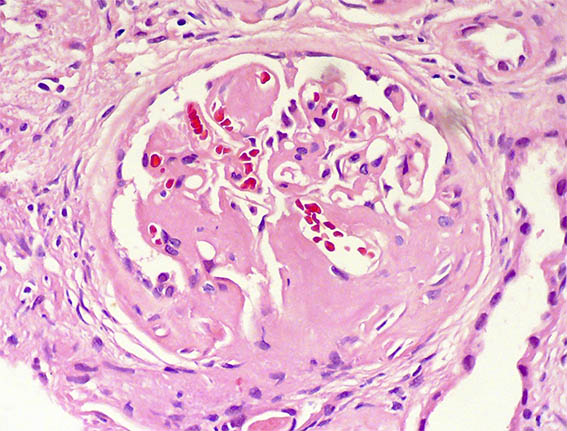

Figura 2.

H&E, X400.